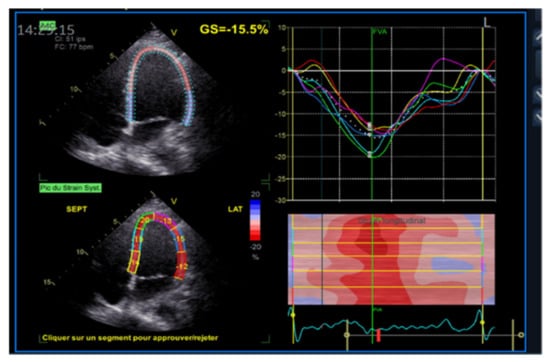

Figure 6. Longitudinal strain measurement in apical 4CH view.

Applsci 11 10549 g006

Figure 7. Strain curves from apical 4CH, 3CH, 2CH to calculate global longitudinal strain (GLS).

3.4. Strain Imaging (STE)

Further knowledge of cardiac function has been acquired using echocardiography strain imaging. Strain and strain rate, which is the first derivative of strain, reflect the deformation and the speed of deformation of myocardial tissue. With these two measures, it is possible to objectively quantify global and segmental myocardial function. The first modality was introduced as a post-processing feature of Doppler myocardial imaging (DMI), with velocity data converted to strain and strain rate curves and color-coded images. More recently we were able to track characteristic speckle patterns created by interference of ultrasound beams in the myocardium, which led to the newest and more reproducible method for strain measurement called speckle-tracking echocardiography. From the accumulative geometrical shift of the speckles, we can calculate the segmental and overall strain and strain rate (Figure 6 and Figure 7). The main advantage of this technique is that it is two-dimensional and angle-independent. When used for the study of the motion of the left ventricle (LV) mechanics, there have been described four principal types of strain or deformation: longitudinal, radial, circumferential, and circumferential–longitudinal shear occurring along with the long axis LV, which results in rotational deformation (twisting and torsion). By applying the same principles of two-dimensional STE, we can access the systolic and diastolic functions of the right ventricle, the left and right atrium [8].